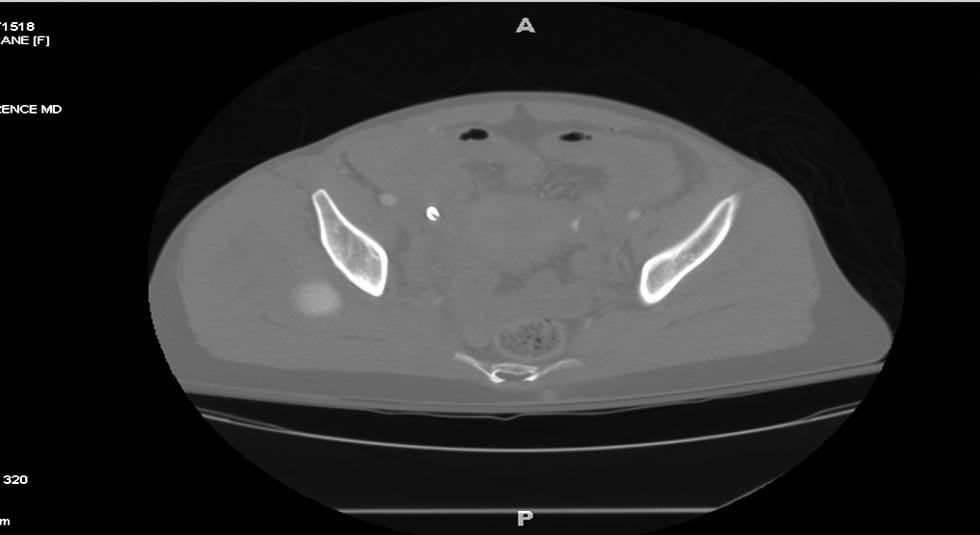

[Ortho] Polytrauma

Вложение не в текстовом формате было извлечено…

Имя     : Picture2.jpg

Тип     : image/jpeg

Размер  : 43279 байтов

Url     : http://weborto.net:8080/pipermail/ortho/attachments/20180407/cb9d5034/attachment-0011.jpg